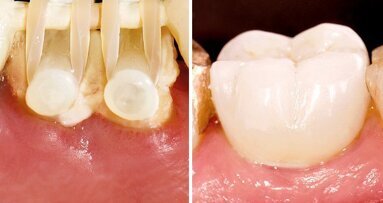

Nachdem die Osseointegration von Implantaten heute gut kalkulierbar ist und auch in kritischen, kompromittierten Situationen gelingt, wendet sich die Aufmerksamkeit nun der Langzeitstabilität des Weichgewebes zu. Das Wechselspiel zwischen marginaler Knochenreaktion und Weichgewebsposition stellt den Schlüssel zur Langzeitstabilität dar. Im anterioren Bereich wird die vertikale Position durch die spätere Position der Mukosa, also aus ästhetischen Gründen bestimmt. Dabei bieten Systeme mit stabiler Ankopplung und Platform Shift mittlerweile überzeugende Daten, sodass ein deutlich geringeres Remodeling auftritt, als die biologische Breite erwarten liesse. Unabhängig davon folgt die vertikale Positionierung im Seitenzahngebiet auch den Gegebenheiten der Höhe und des Platzangebotes der späteren Versorgung.